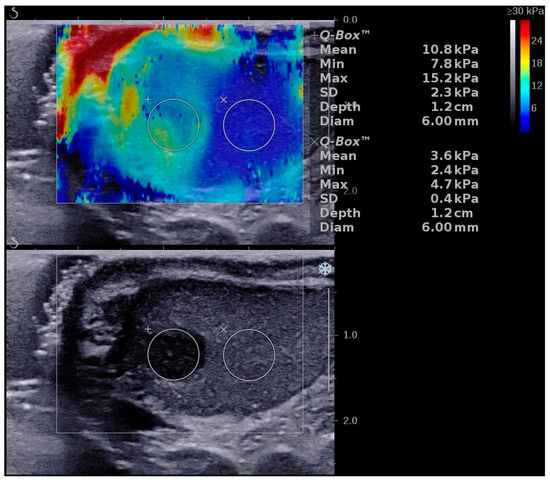

2D SWE and RTE